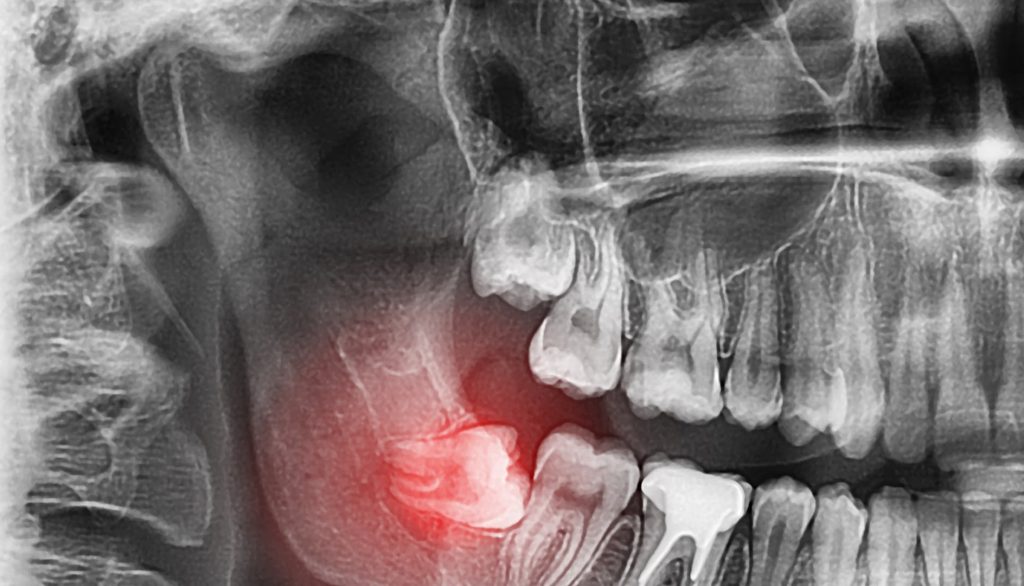

While dentists always aim to save natural teeth whenever possible, sometimes removal is the healthiest choice. Common reasons for extraction include severe decay, advanced gum disease, fractures below the gumline, or impacted wisdom teeth that threaten neighboring teeth.

There are two main types of extractions. A simple extraction is performed when the tooth is visible and can be removed with standard instruments. A surgical extraction is required if the tooth is broken, impacted, or not fully erupted, and may involve small incisions or sectioning the tooth for safe removal.